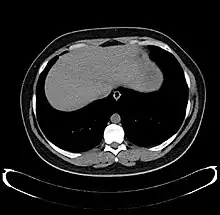

The diagnosis of liver disease is made by liver function tests, groups of blood tests, that can readily show the extent of liver damage. If infection is suspected, then other serological tests will be carried out. A physical examination of the liver can only reveal its size and any tenderness, and some form of imaging such as an ultrasound or CT scan may also be needed.

Axial CT image showing anomalous hepatic veins coursing on the liver's subcapsular anterior surface[66]

Maximum intensity projection (MIP) CT image as viewed anteriorly showing the anomalous hepatic veins coursing on the anterior surface of the liver

Lateral MIP view in the same patient as previous image

A CT scan in which the liver and portal vein are shown